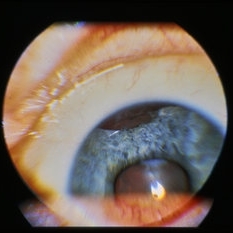

Anterior segment image with subconj heme.

Condition/keywords: trauma